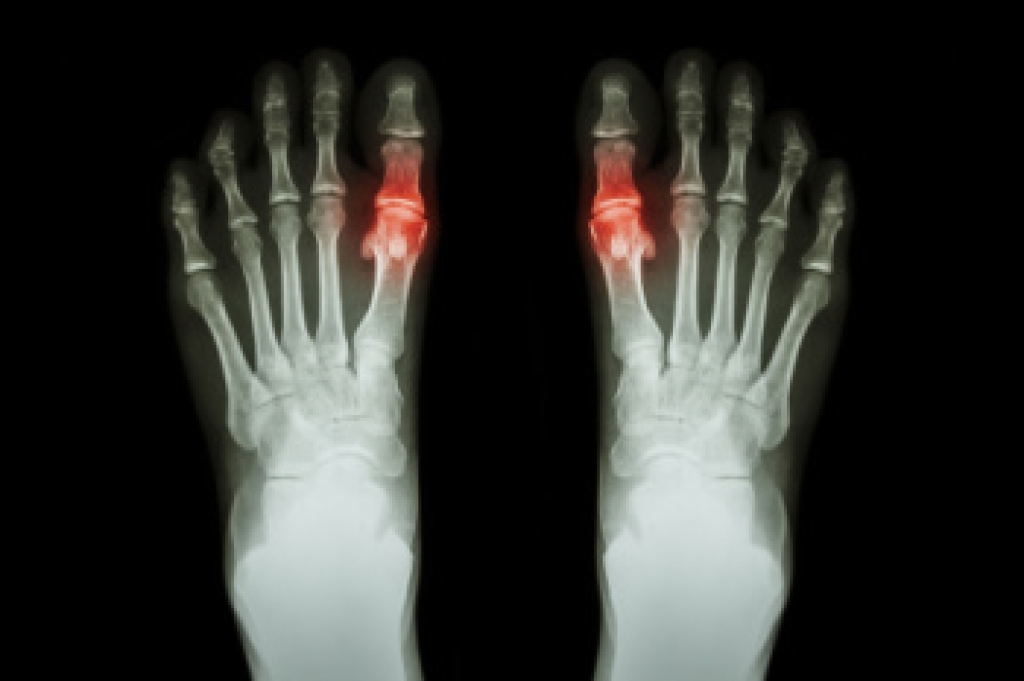

Ingrown toenails occur when a toenail grows sideways into the bed of the nail, causing pain, swelling, and possibly infection.

- Bacterial infections